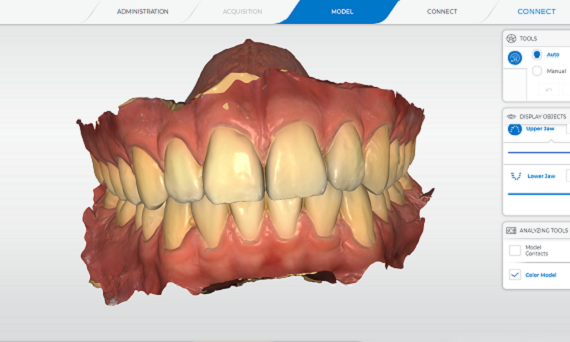

Quelle que soit la façon dont vous souhaitez concevoir vos flux de travail, nos scanners dentaires intra-oraux optimisés par DS Core constituent un point de départ idéal pour la dentisterie numérique de votre cabinet, en collaboration avec vos partenaires préférés. Ils rendent la prise d’empreinte plus facile, plus intuitive et ergonomique que jamais. La précision des modèles 3D aux couleurs naturelles vous impressionnera, vous et vos patients.

- Réalisez et étiquetez des modèles numériques rapidement et simplement à des fins d’archivage

- Des résultats reproductibles prévisibles

Excellents résultats de scan

Grâce à la précision et à la qualité fiables exceptionnelles de Primescan et Primescan Connect, vous pouvez être certain que c'est le choix idéal pour obtenir un ajustement parfait dans n'importe quelle restauration ou appareil. Votre laboratoire appréciera la qualité de vos modèles numériques.